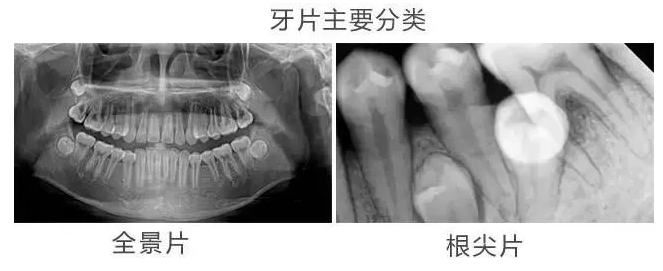

我们常说的「拍牙片」只是一个统称,具体指一切口腔X线片检查,并不是单指一张片子。需要根据不同情况来选择拍摄哪种牙片。

一般来说,我们所说的牙片由以下几种组成:

△其优点在于1:1还原牙齿的大小,成像速度快,对于单颗牙齿情况的检查相对细致。

△优点在于可以了解牙根下是否有囊肿,周围骨头是否吸收,牙槽骨内是否有埋伏牙、多生牙等。